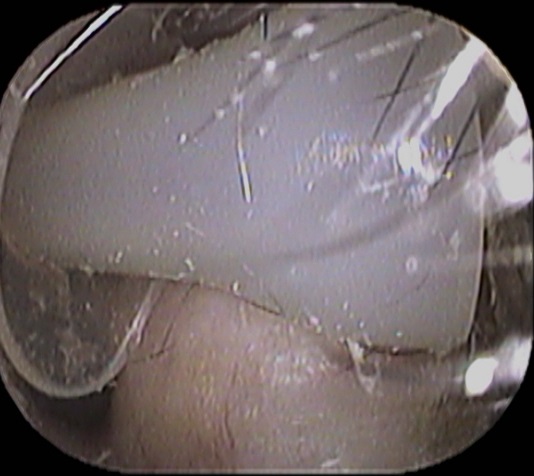

先日のことです。「耳

の痒み」を主訴に当院受診された患者さんがおられました。

耳

を診てみると

何か白い物体が・・

「イヤチップ」と呼ばれているシリコン製の耳栓パーツです。

本来はこの位置にあります↓

何かの拍子に外れてしまったようです。

耳症状が気になる方は、耳鼻咽喉科の受診をオススメいたします。